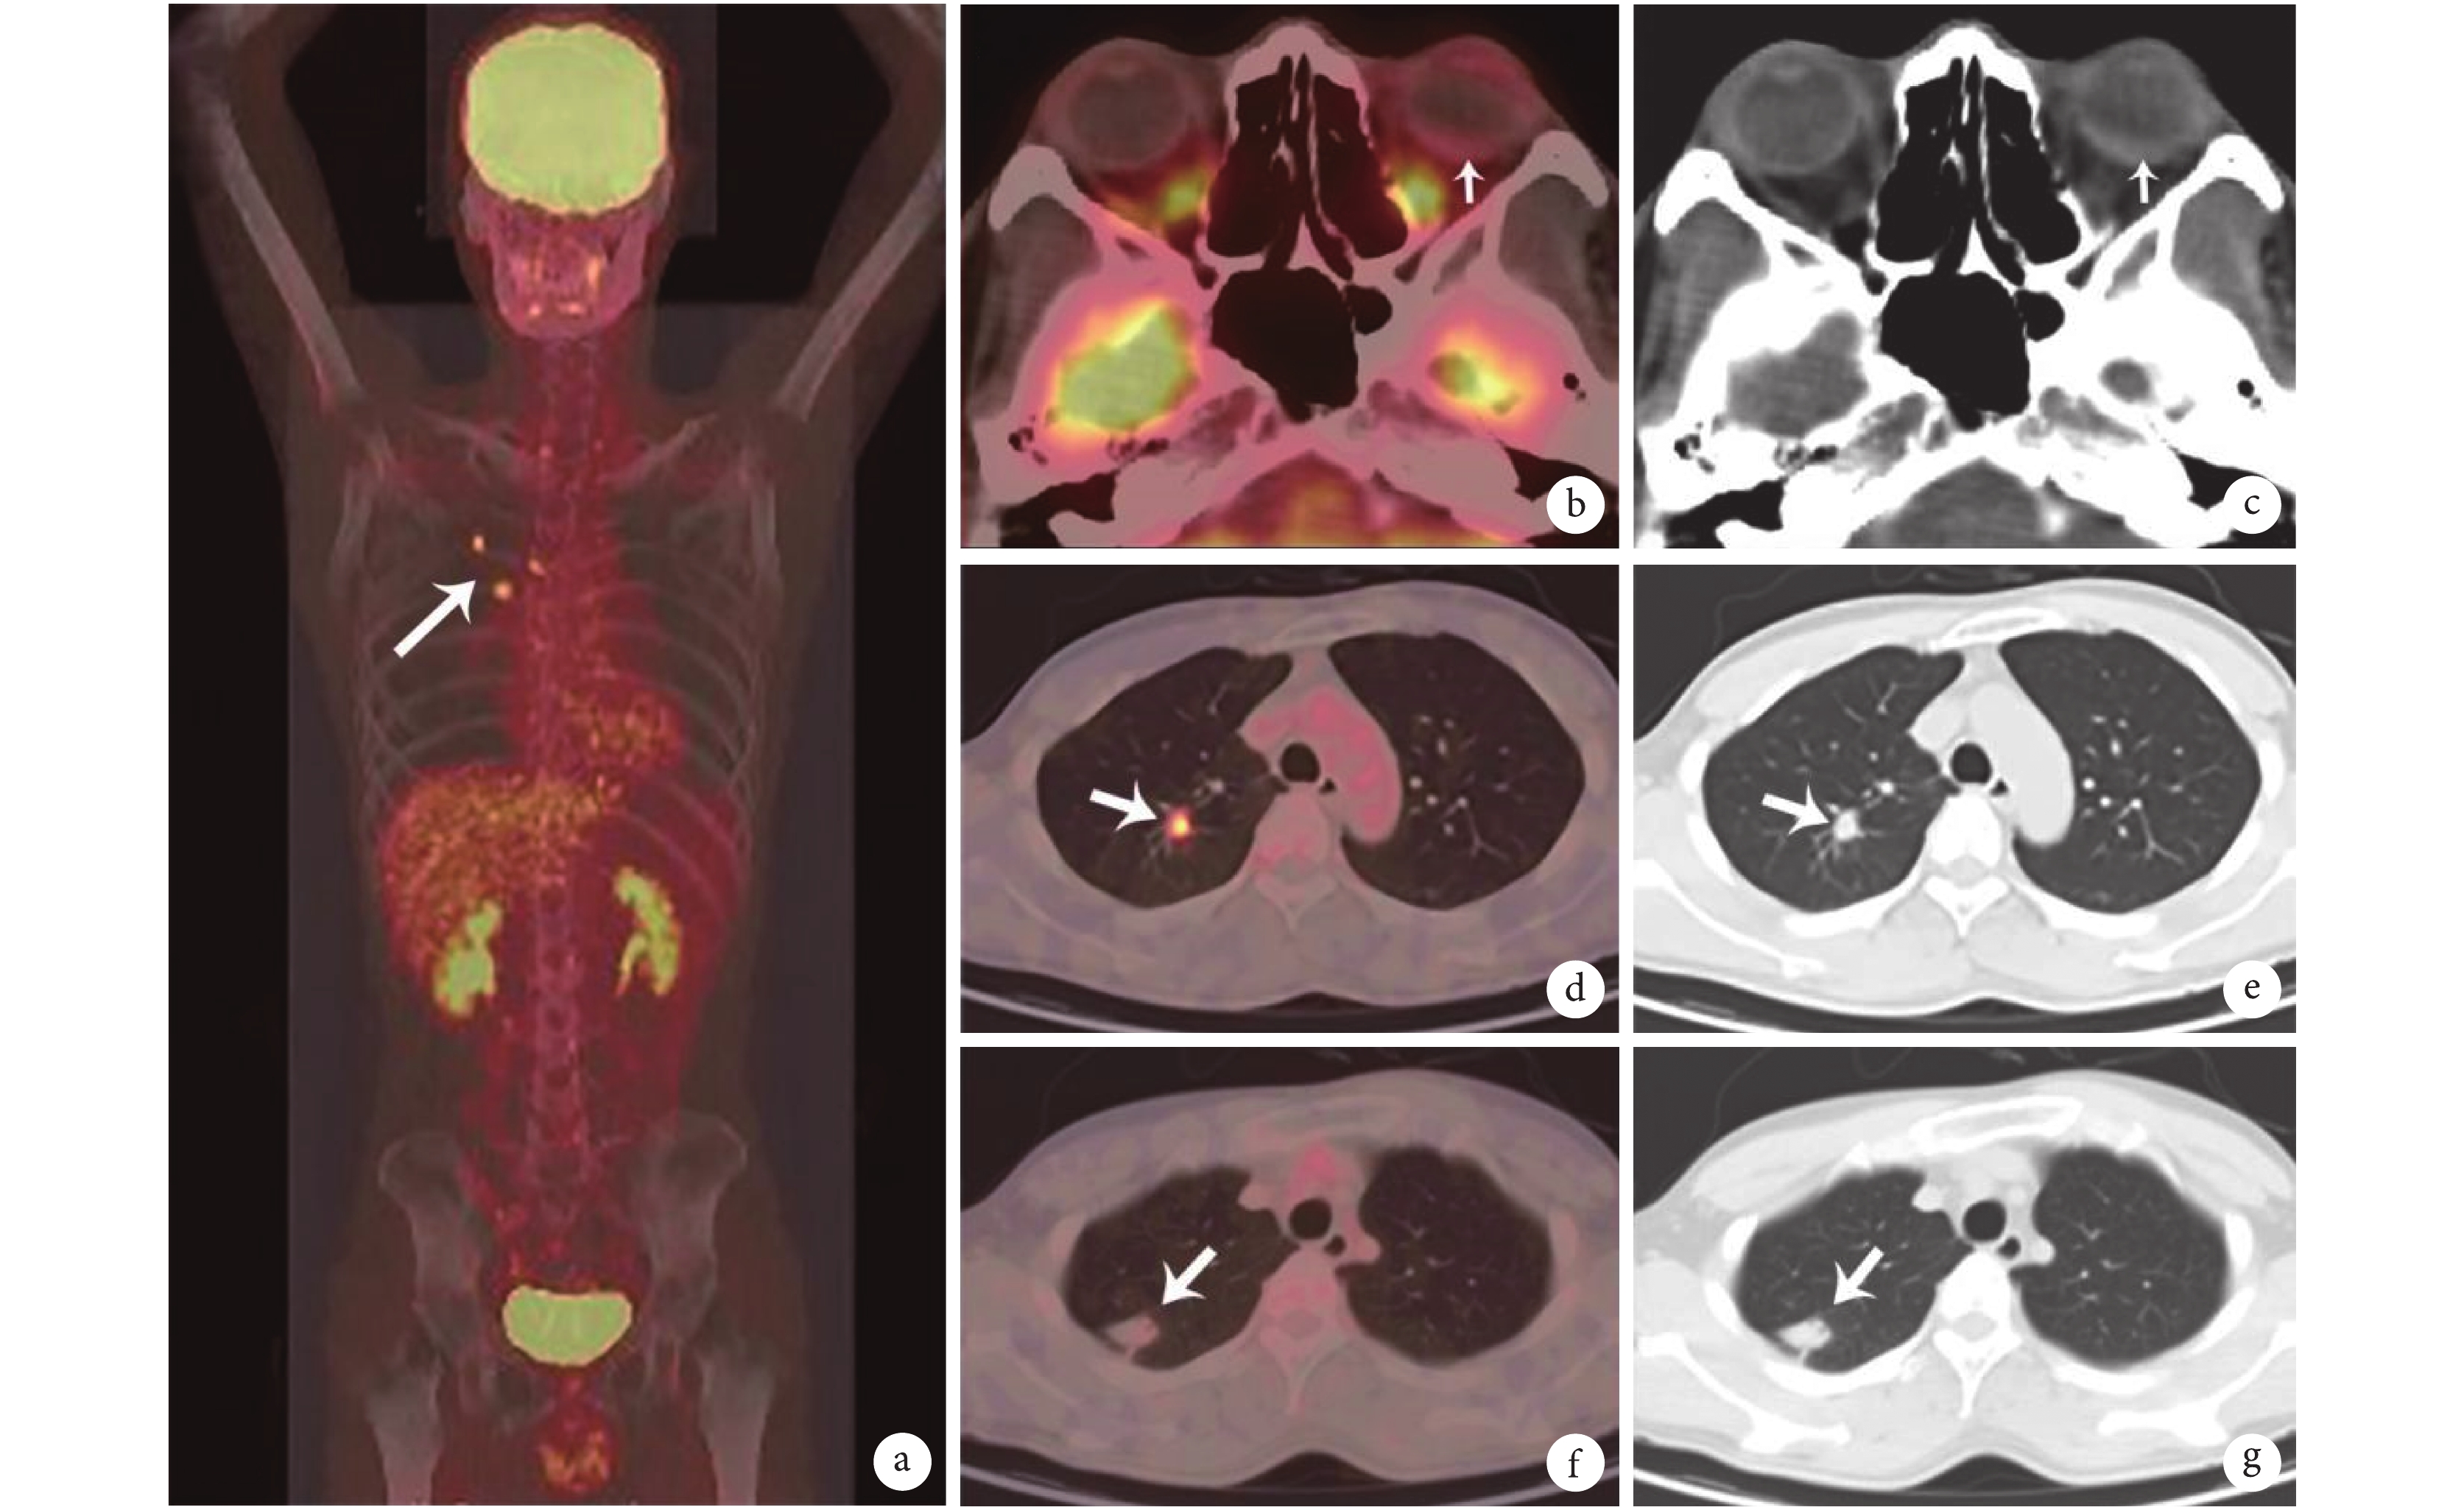

由于患者拒絕侵入性檢查,行全身氟代脫氧葡萄糖(FDG)PET-CT 檢查,結果提示多個縱隔淋巴結輕度攝取增高(圖 2a),雙眼球內未見 FDG 高攝取(圖 2b、c),右肺上葉尖后段病灶輕度 FDG 攝取增高(圖 2d、e),右肺上葉近胸膜病灶無攝取增高(圖 2f、g)。其余部位未見病理性 FDG 高攝取。

示肺門多個淋巴結 FDG 攝取輕度增高(a。箭指示處的淋巴結 SUVmax 4.0),雙眼無 FDG 高攝取(b、c),右肺上葉尖后段病灶 FDG 輕度攝取增高(d、e。箭指示處的病灶 SUVmax 3.5),右肺周邊片狀病灶無 FDG 高攝取(f、g)